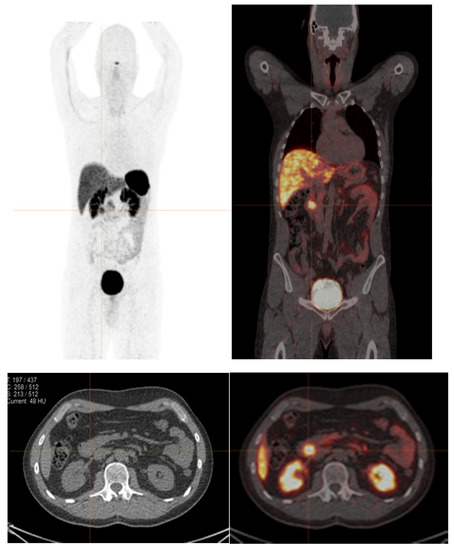

1.5. Diagnostic Value of Combined 68Ga SSTR and 18F-FDG PET in GEP-NENs

2. Dual PET Imaging Grading System

2.1. The NETPET Score

2.2. Three-Scale Grading System